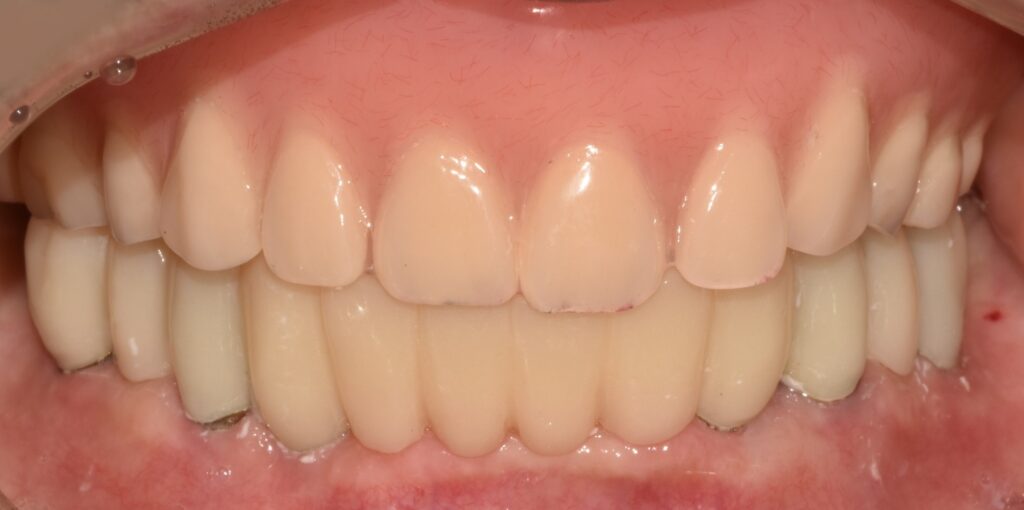

보철까지 잘 완성하다.

임플란트 보철까지 깔끔하게 잘 올라간 모습을 볼 수 있습니다.

​또한 상악동 거상술을 이용해 만든 뼈도 단단하게 자기 뼈가 되고 있는 모습을 볼 수 있습니다.

​치료 후 고기를 너무 잘 드셔서 금방 살이 찌고 건강한 모습을 보여주셔서 매우 반가웠던 기억이 나네요.